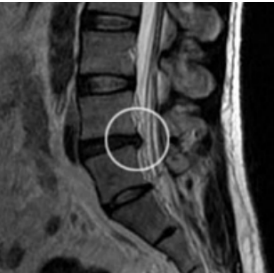

Q

hernia de disco

aonde esta a hernia?

que exame é esse?

A

Hérnia de disco C5 - C6: RM em T2